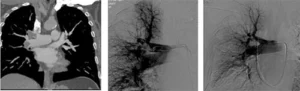

L’embolia polmonare è una patologia grave che si verifica quando una o più arterie polmonari sono bloccate da un embolo, un coagulo di sangue che ostacola il normale flusso sanguigno verso i polmoni, impedendo il passaggio di ossigeno e compromettendo la funzione respiratoria. Questo può causare difficoltà respiratorie, dolore al petto e, se non trattata tempestivamente, può evolvere in infarto polmonare o persino portare alla morte.

Embolia polmonare massiva: si verifica quando un trombo di grandi dimensioni occlude una delle principali arterie polmonari, determinando un episodio acuto potenzialmente letale.